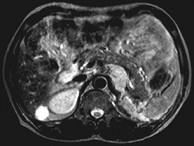

问题 女,34岁,无意中发现血压升高4个月就诊,行CT检查,如图所示,下列说法正确的是 ( )

选项 A、考虑为左肾上腺嗜铬细胞瘤 B、考虑为左肾上腺转移瘤 C、增强扫描,该病灶周边明显强化,中心处强化不明显 D、考虑为左肾上腺腺瘤 E、CT示左侧肾上腺区可见一等密度块影,边界清楚

答案 ACE